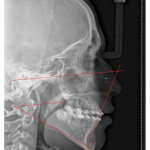

- Ricketts